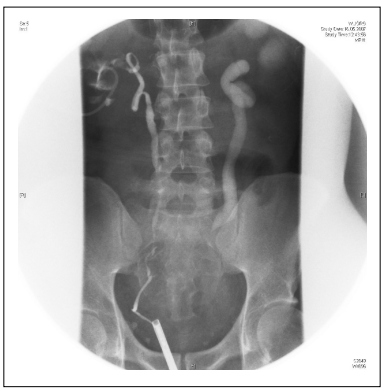

JW, a 37-year-old male presented with a chronic urinary infection. The patient has undergone a prophylactic total colectomy 10 years before for familial polyposis coli. Following surgery, the patient developed ureteral stricture bilaterally, that were managed by introducing ureteral double-J (DJ) stents bilaterally. The renal scintigraphy showed a severely reduced renal function over time, which finally resulted in 13% on the left side and 87 % on the right side. Physical examination was normal. Blood count, serum creatinine, and blood urea nitrogen (BUN) were normal. After placement of two percutaneous nephrectomies, the patient underwent an antegrade (APG) and retrograde ureteropyelography (UPG); both diagnostic procedures revealed bilateral hydroureteronephrosis with multiple right ureteral strictures (Figure 1).

Figure 1. Antegrade and retrograde ureteropyelography showing bilateral hydronephrosis with multiple right ureteral stenoses.